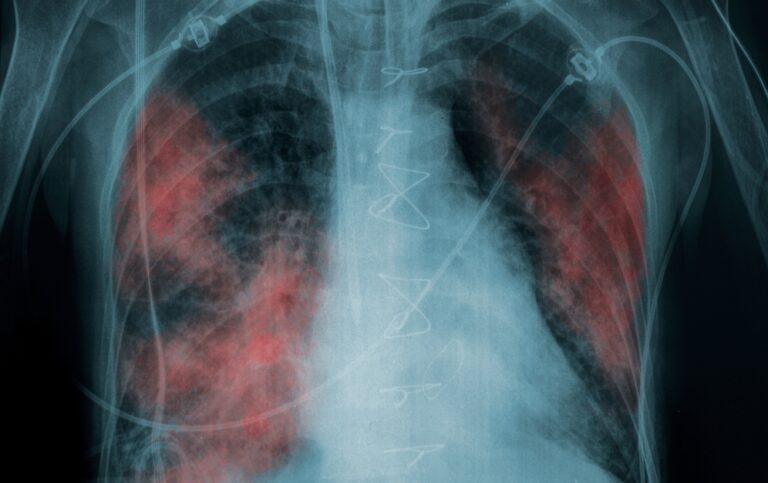

TBC megbetegedést igazoltak az egyik vásárhelyi iskola dolgozójánál!